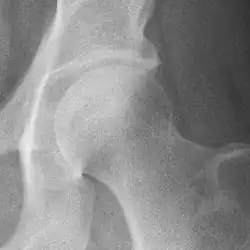

The most commonly used radiographic classification system for osteoarthritis of the hip joint is the Kellgren–Lawrence system (or KL system).[6] It uses plain radiographs.

Osteoarthritis of the hip joint may also be graded by Tönnis classification. There is no consensus whether it is more or less reliable than the Kellgren-Lawrence system.[8]

Severe (Tönnis grade 3) osteoarthritis of the hip.

severe joint space narrowing, or joint space obliteration

severe deformity of the head